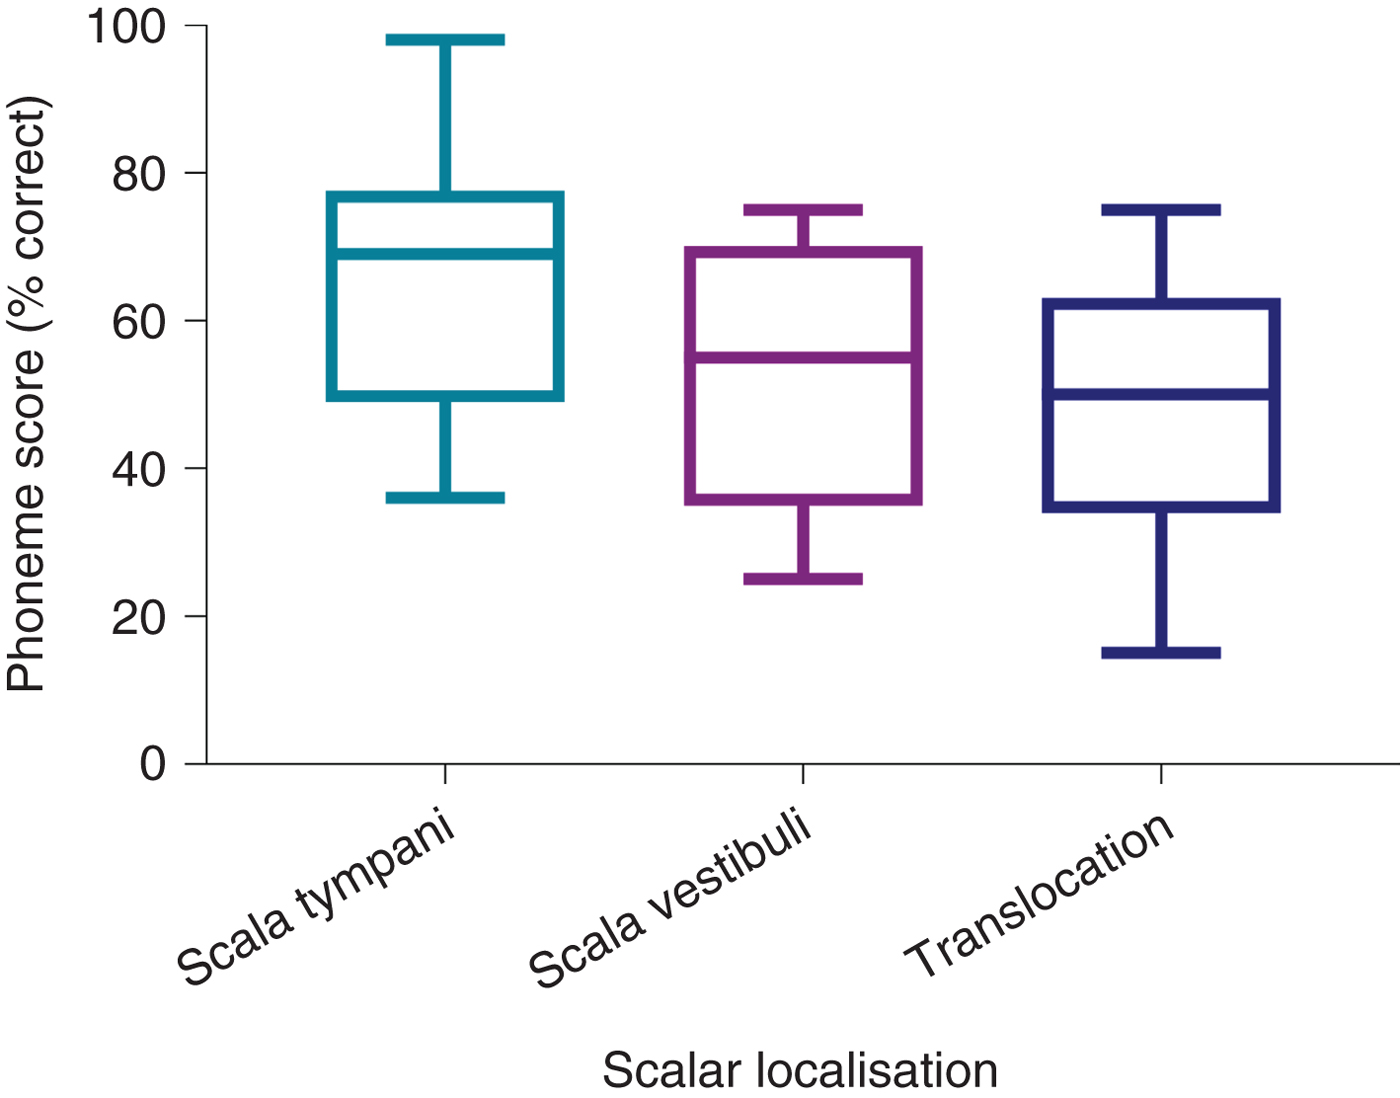

Comparison of post-operative phonemes scores between the CI512 electrode localisation groups revealed better scores for scala tympani localisation, at 3 and 12 months post-implantation, but without statistical significance (Table 2 and Figure 5). When the pre-lingual patients were excluded and the post-lingual patients analysed, there were significant differences between the scala tympani group and the other two groups (scala vestibuli and translocation) (p = 0.013). These differences were significant at 12 months post-implantation. Post-hoc analysis demonstrated significant differences between scala tympani and scala vestibuli groups (69.1 per cent vs 54.2 per cent; p < 0.05) and between scala tympani and translocation groups (69.1 per cent vs 50 per cent; p < 0.005) at 12 months post-implantation, but without significant differences between scala vestibuli and translocation groups (Table 3 and Figure 6).

Fig. 5. Twelve-month post-implantation phonemes scores of all patients with CI512 electrodes according to scalar localisation.

Fig. 6. Twelve-month post-implantation phonemes scores of post-lingual patients with CI512 electrodes according to scalar localisation.

The degree to which scalar localisation contributes to the speech recognition outcome is the most relevant endpoint for clinicians. Our findings demonstrated that intracochlear electrode placement has a significant influence on the variability of post-implantation speech recognition results. There was a trend toward better consonant–vowel–consonant word scores for the complete scala tympani insertion group of combined pre- and post-lingual recipients, compared to the scala vestibuli and translocation groups, but this did not reach significance. Analysis of the scala tympani group revealed a much higher proportion of pre-lingual recipients, which may explain the poorer results for that group. Previous studies examining scalar localisation have reported outcomes for post-lingual recipients only.

Given that poorer outcomes are expected in recipients with a pre-lingual component to their hearing loss, a further analysis that included only post-lingual recipients was performed, in order to minimise the variables. This comparison demonstrated that the scala tympani group speech performance scores were higher by 15 per cent on average, compared to the scala vestibuli group. Moreover, according to the regression analysis model, electrodes located in scala vestibuli, or translocated from scala tympani to scala vestibuli, independently reduced the 12-month post-implantation phoneme scores by 10.5 per cent, while no significant difference was found between scala vestibuli and translocation localisation.